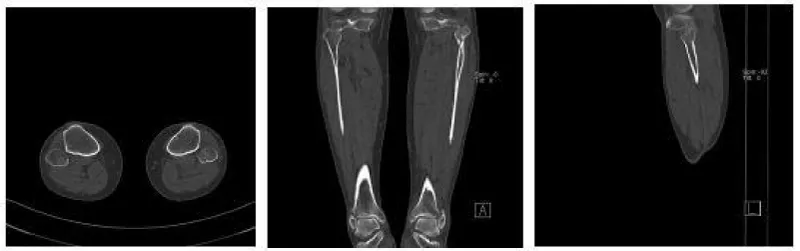

The anesthetic for the operation was lumbar anesthesia. A posterolateral approach was used to expose the Volkmann fracture. An anterior tibial approach was used to expose the Tillaux-Chaput fracture. The inferior tibiofibular joint was checked carefully. Fractures were reduced and then fixed. Volkmann fracture was fixed by buttress plate, and Tillaux-Chaput fracture was performed by hollow screw. Hook test intraoperative was negative. Anatomical reduction and perfect stability were confirmed by X and CT postoperatively (Figures 6.7). CT scan in the transverse section confirmed that the anterior and posterior edge of the distal fibula is in an arc with the fractures of the tibia. It meant there was no dislocation of the distal fibula. The anterior and posterior ligaments of the inferior tibiofibular ligament are in good condition.

Three weeks after surgery, the patient is required to touch down weight-bearing in a plaster splint. Patients are then allowed partial weight-bearing after six weeks and progress to weight-bearing. Ankle joint function exercises can be done three weeks after surgery. X noted that the fracture healed without shortening or rotation of the fibula when twelve weeks after surgery (Figure 8). The AOFAS score is 92 at twelve weeks follow-up [7,8].